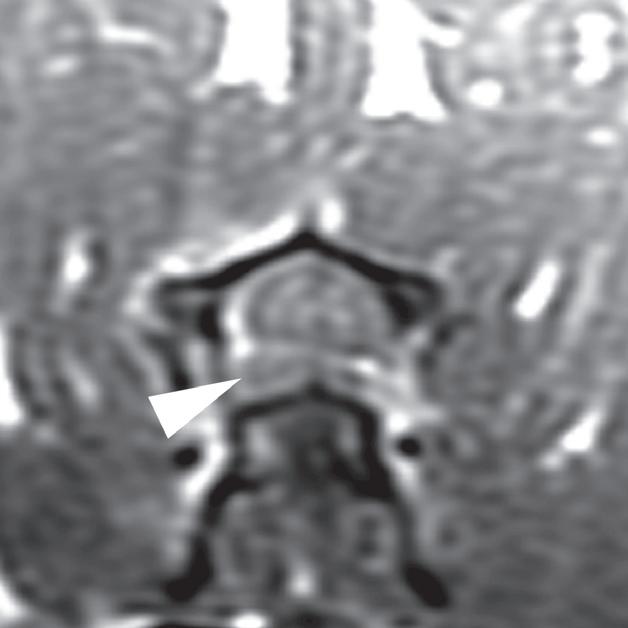

Rycina

3.2.8. Podwichnięcie kręgów szyjnych ze złamaniem wyrostka stawowego (pies) TK i MR

Badania wykonano u 5-letniej samicy mieszańca w typie teriera, która została pogryziona w okolicy szyjnej przez większego psa tego samego dnia, w którym wykonano badania. Podczas wizyty u psa zaobserwowano deficyty neurologiczne z neuroanatomiczną lokalizacją w obrębie C6–T2. Radiogramy przeglądowe ukazały grzbietowe podwichnięcie kręgu C7 względem C6 oraz zwężenie przestrzeni międzykręgowej C6–C7 (a – grot strzałki). Podobne zmiany uwidoczniono na obrazach TK w projekcji strzałkowej i 3D (b, f – grot strzałki). Dodatkowo stwierdzono wieloodłamowe złamanie z przemieszczeniem prawego doczaszkowego wyrostka stawowego kręgu C7 (c–e – strzałka). Dla porównania przedstawiono prawidłowy lewy wyrostek stawowy (f – strzałka). W badaniu MR przestrzeń międzykręgowa C6–C7 była zwężona i wykazywała obniżoną intensywność sygnału w obrazach T2-zależnych (i – strzałka), a przemieszczony materiał dyskowy znajdował się w prawej dobrzusznej części kanału kręgowego (g, h – grot strzałki). W obrazach występują cechy ucisku na rdzeń kręgowy (g–i) oraz zwiększona intensywność sygnału w sekwencji T2-zależnej w obrębie rdzenia na poziomie C6–C7 (h, i), co wskazuje na jego uszkodzenie wewnętrzne. Materiał dyskowy został chirurgicznie usunięty z kanału kręgowego, a podwichnięcie zredukowano i ustabilizowano operacyjnie